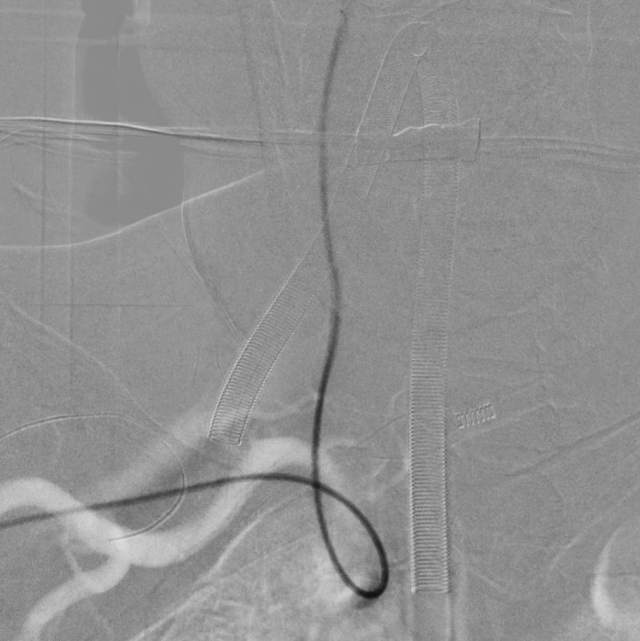

近日,老人家恢复了差不多了,为了防治日后宽颈的脑动脉瘤复发,还需要稍微进行一下修修补补,减少血流对薄弱的脑动脉瘤的冲击,那就需要再简单加固一下。

这个加固的材料呢,放进血管后,慢慢会被自己的内皮细胞覆盖,变成自己身体的一部分,还能防止动脉瘤复发,是一个非常好的装备。

装备虽好,那还的找靠谱的医生给安装进去吧。今日,我们顺利为老人家在病变部位的血管植入了血流导向装置,手术顺利。然而,不是每一个破裂的脑动脉瘤患者像老人家一样这么幸运,能够有机会赶到医院,得到及时的治疗……